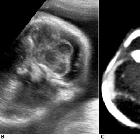

Antenatal ultrasound

Thus identification of a dividing membrane or two placentas excludes the diagnosis. Definitive sonographic features will depend on the type of fusion.

General features include:

- lack of a separating inter-twin membrane

- non-separable skin contours with an inability to separate the fetal bodies

- detection of other anomalies in a twin gestation

- solitary umbilical cord with more than 3 vessels present

- both fetal heads persistently at the same level

- backward flexion of the cervical spine (due to the fact that most conjoined twins are fused ventrally and face each other

- bibreech or less commonly, bicephalic presentation

- constant relative fetal positions